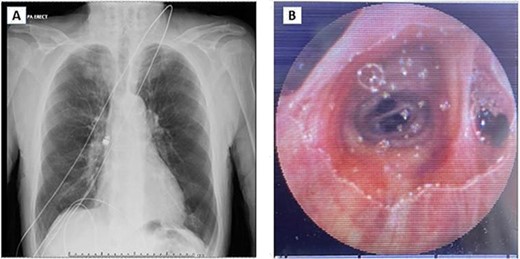

An 87-year-old gentleman was investigated for anaemia, and a positive faecal blood test was booked for capsule endoscopy. This was done as an outpatient procedure using a Pillcam SB 3 system (Medtronic, MN, USA). After necessary directions, the patient was asked to swallow the capsule. Following swallowing of the capsule, the patient started to cough intermittently and desaturated requiring supplemental oxygen. On the monitor, the capsule was not moving and did not appear to be in the oesophagus. Chest X-ray confirmed the pill was in the right main bronchus (Fig. 1A). The patient was then referred to the Thoracic Surgical service for urgent evaluation and management.

(A) Chest X-ray showing capsule in the right main bronchus. (B) Capsule lodged in bronchus intermedius showing endobronchial anatomy.